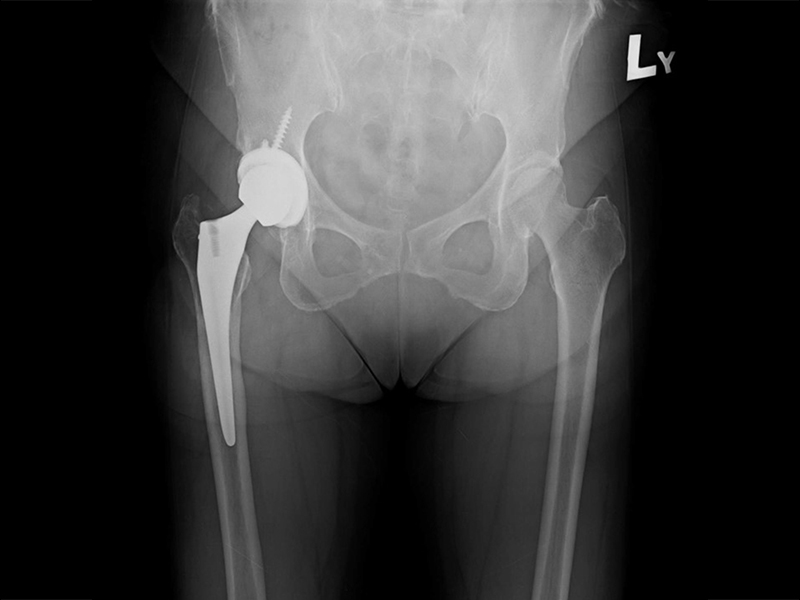

機器手臂手術